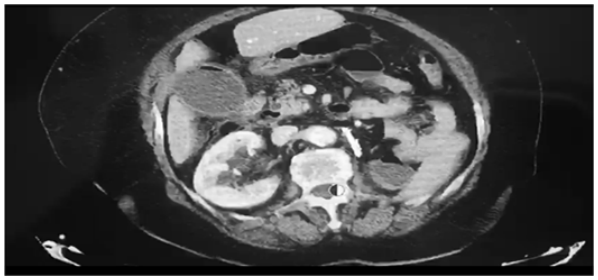

Um paciente de 82 anos de idade, com colecistite aguda, apresenta confusão mental, hipotensão refratária a cristaloide e leucocitose de 22 mil, com creatinina de 2,5 g/dl. Tem antecedente de infarto de miocárdio há dois anos, diabete e hipertensão. Realizou a tomografia abaixo para ajudar na orientação.

Com base nesse caso hipotético, assinale a alternativa correta quanto à melhor opção.